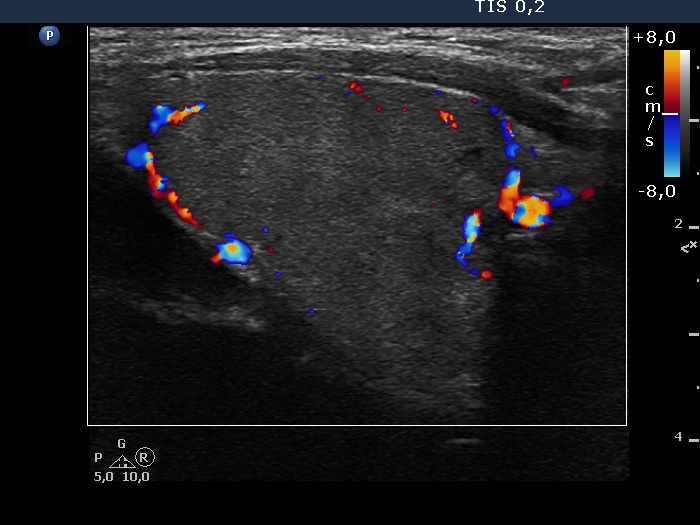

Right lobe, longitudinal scan

Right lobe, longitudinal view, color Doppler mode. The lesion has perinodular blood flow.